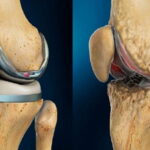

بخشی از نمونه کارها

نمونه کارهای قبل و بعد